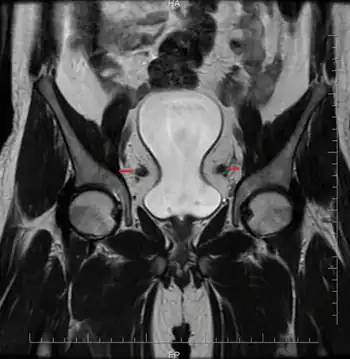

| MRI pelvis shows pelvic lipomatosis compressing the bladder and ‘eye’ formed by dilated vas | |

It is associated with cystitis glandularis, a precursor to adenocarcinoma of the urinary bladder. It is associated with deposition of mature unencapsulated fat in the retroperitoneal pelvic space producing the typical "pear-shaped" appearance of the bladder on CT scan. This condition also causes a straightening and tubular appearance of the rectum.